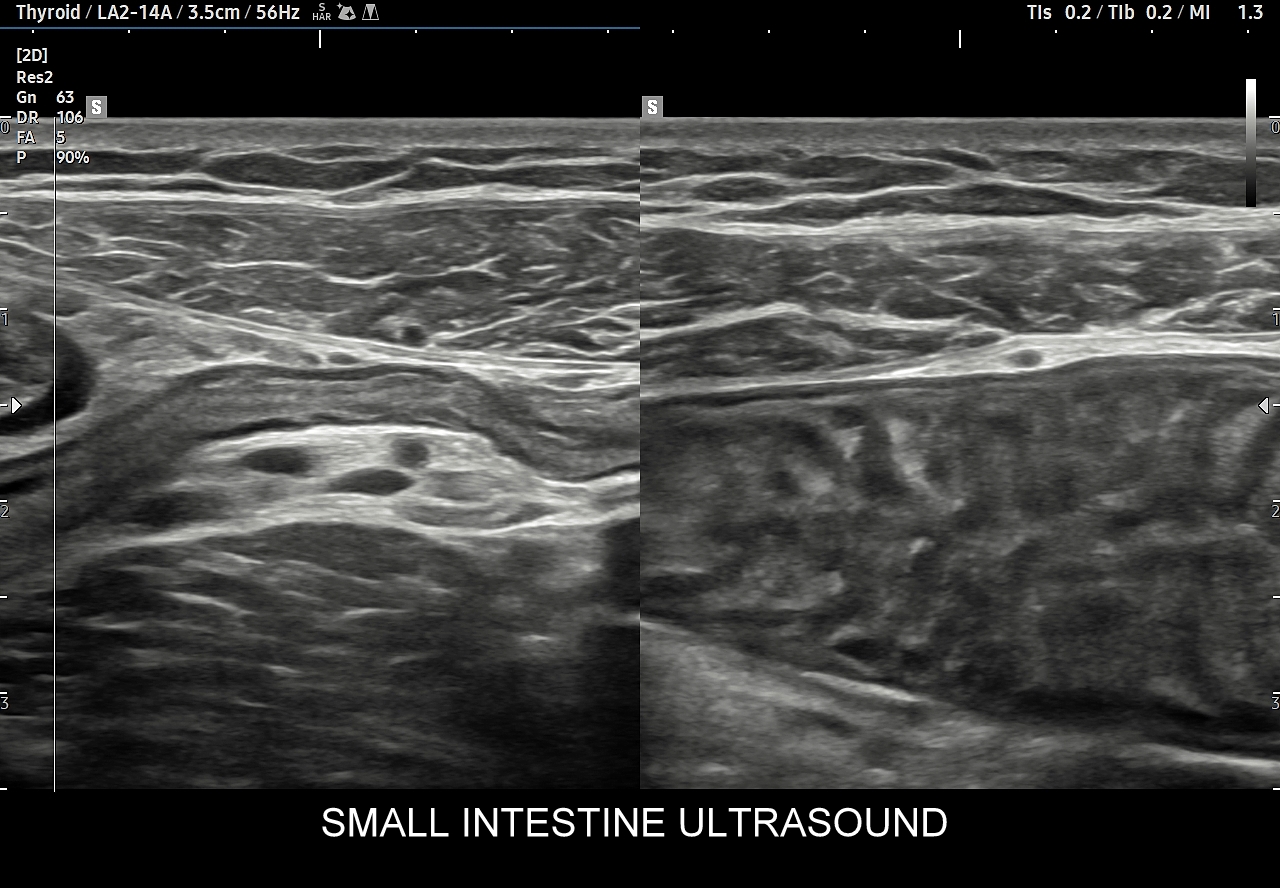

Jeśli uczestniczyli już Państwo w kursie USG brzucha, a wciąż potrzebujecie porady, jak praktycznie w badaniu USG zlokalizować wpust żołądka, dwunastnicę, jelito czcze, kręte, czy wyrostek robaczkowy, żyłę pępkową, przewód żółciowy wspólny, ogon trzustki, torbę sieciową, sieć mniejszą, sieć większą, krezkę brzuszną, krezkę jelita cienkiego, tętnice nerkowe, tętnice trzewne, jak zróżnicować trzustkę od pseudotrzustki, jak wykryć przepuklinę, czy ocenić kresę białą to praktyczne szkolenie USG obszaru brzucha Cedum ® będzie odpowiednim wyborem!